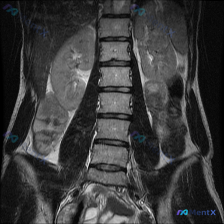

网上看到一份肾脏MRI T2加权冠状位影像,先整理下关键信息:

影像核心发现:

- 双肾体积增大,呈“分叶状”,表面凹凸不平

- 双肾实质内弥漫大量圆形/椭圆形高信号囊泡,与尿液信号一致

- 正常皮髓质分界模糊,集合系统受推挤变形

- 未见明显囊壁增厚、结节或实性成分(平扫下)

额外关联线索:

影像阅片时同时提到了“脊柱侧弯”的观察方向,提示二者可能存在关联